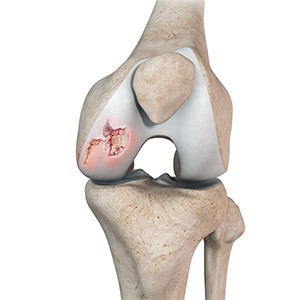

Picture of Osteochondritis Dissecans

Osteochondritis Dissecans

Osteochondritis dissecans is a joint condition in which a piece of cartilage, along with a thin layer of the bone separates from the end of the bone because of inadequate blood supply. The separated fragments are sometimes called “joint mice”. These fragments may be localised, or may detach and fall into the joint space causing pain and joint instability.